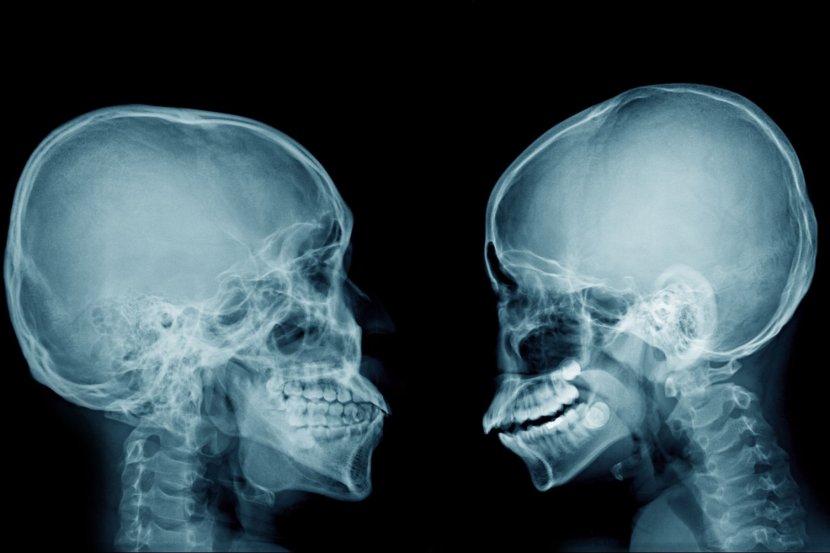

Zubi nisu kosti, iako se delimično sastoje od dentina – supstance tvrđe od kosti, ali, i pored toga osteoporoza može da utiče na njih na nekoliko načina

Zubi nisu kosti (iako se delimično sastoje od dentina – supstance tvrđe od kosti, i protežu se do vilice), ali i pored toga osteoporoza može da utiče na njih na nekoliko načina. Osteoporoza može da oslabi kost vilice i olabavi zube.  Takođe, može da utiče i na druge delove usta, uključujući vilicu i desni.